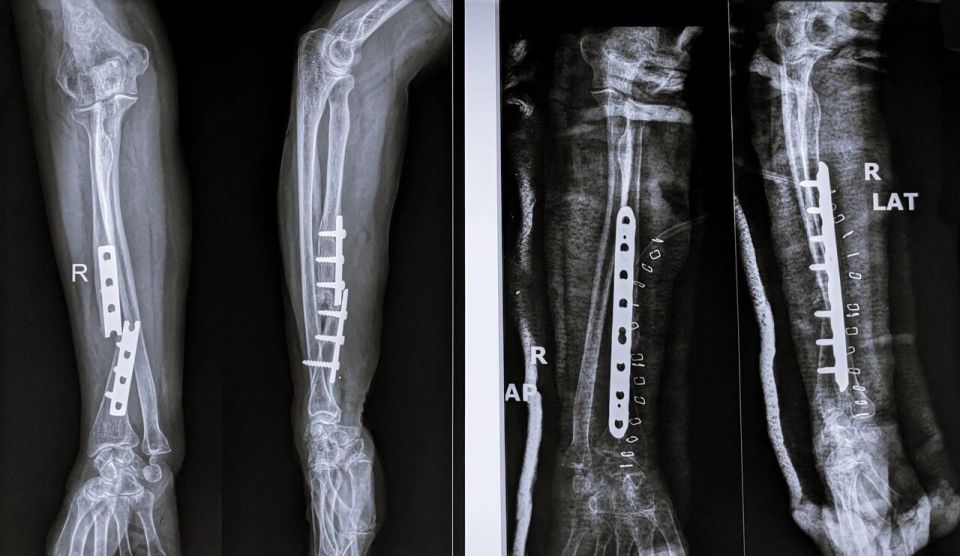

在传统手术疗法中,往往需要将骨块复位后,再使用钢板、螺钉等将其固定,听上去就令人头皮发麻。

打完钢板、螺钉后的骨头

图片来源:图虫创意

而且,有部分骨折并不是打完钢板钢钉就一劳永逸,还需要二次手术取出内固定物,这更是增加了患者的痛苦。如何提供更有效、微创的治疗方案,成为该领域最具挑战性的问题之一。